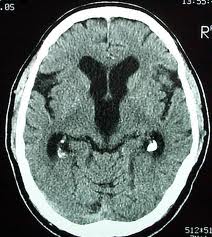

Untuk mendiagnosis kemungkinan seseorang menderita NPH, maka beberapa pemeriksaan dapat dilakukan seperti pemeriksaan CT Scan kepala atau pemasangan monitor tekanan intrakranial untuk mengevaluasi fkutuasi dari tekanan di dalam kepala.

Normal Pressure Hydrocephalus